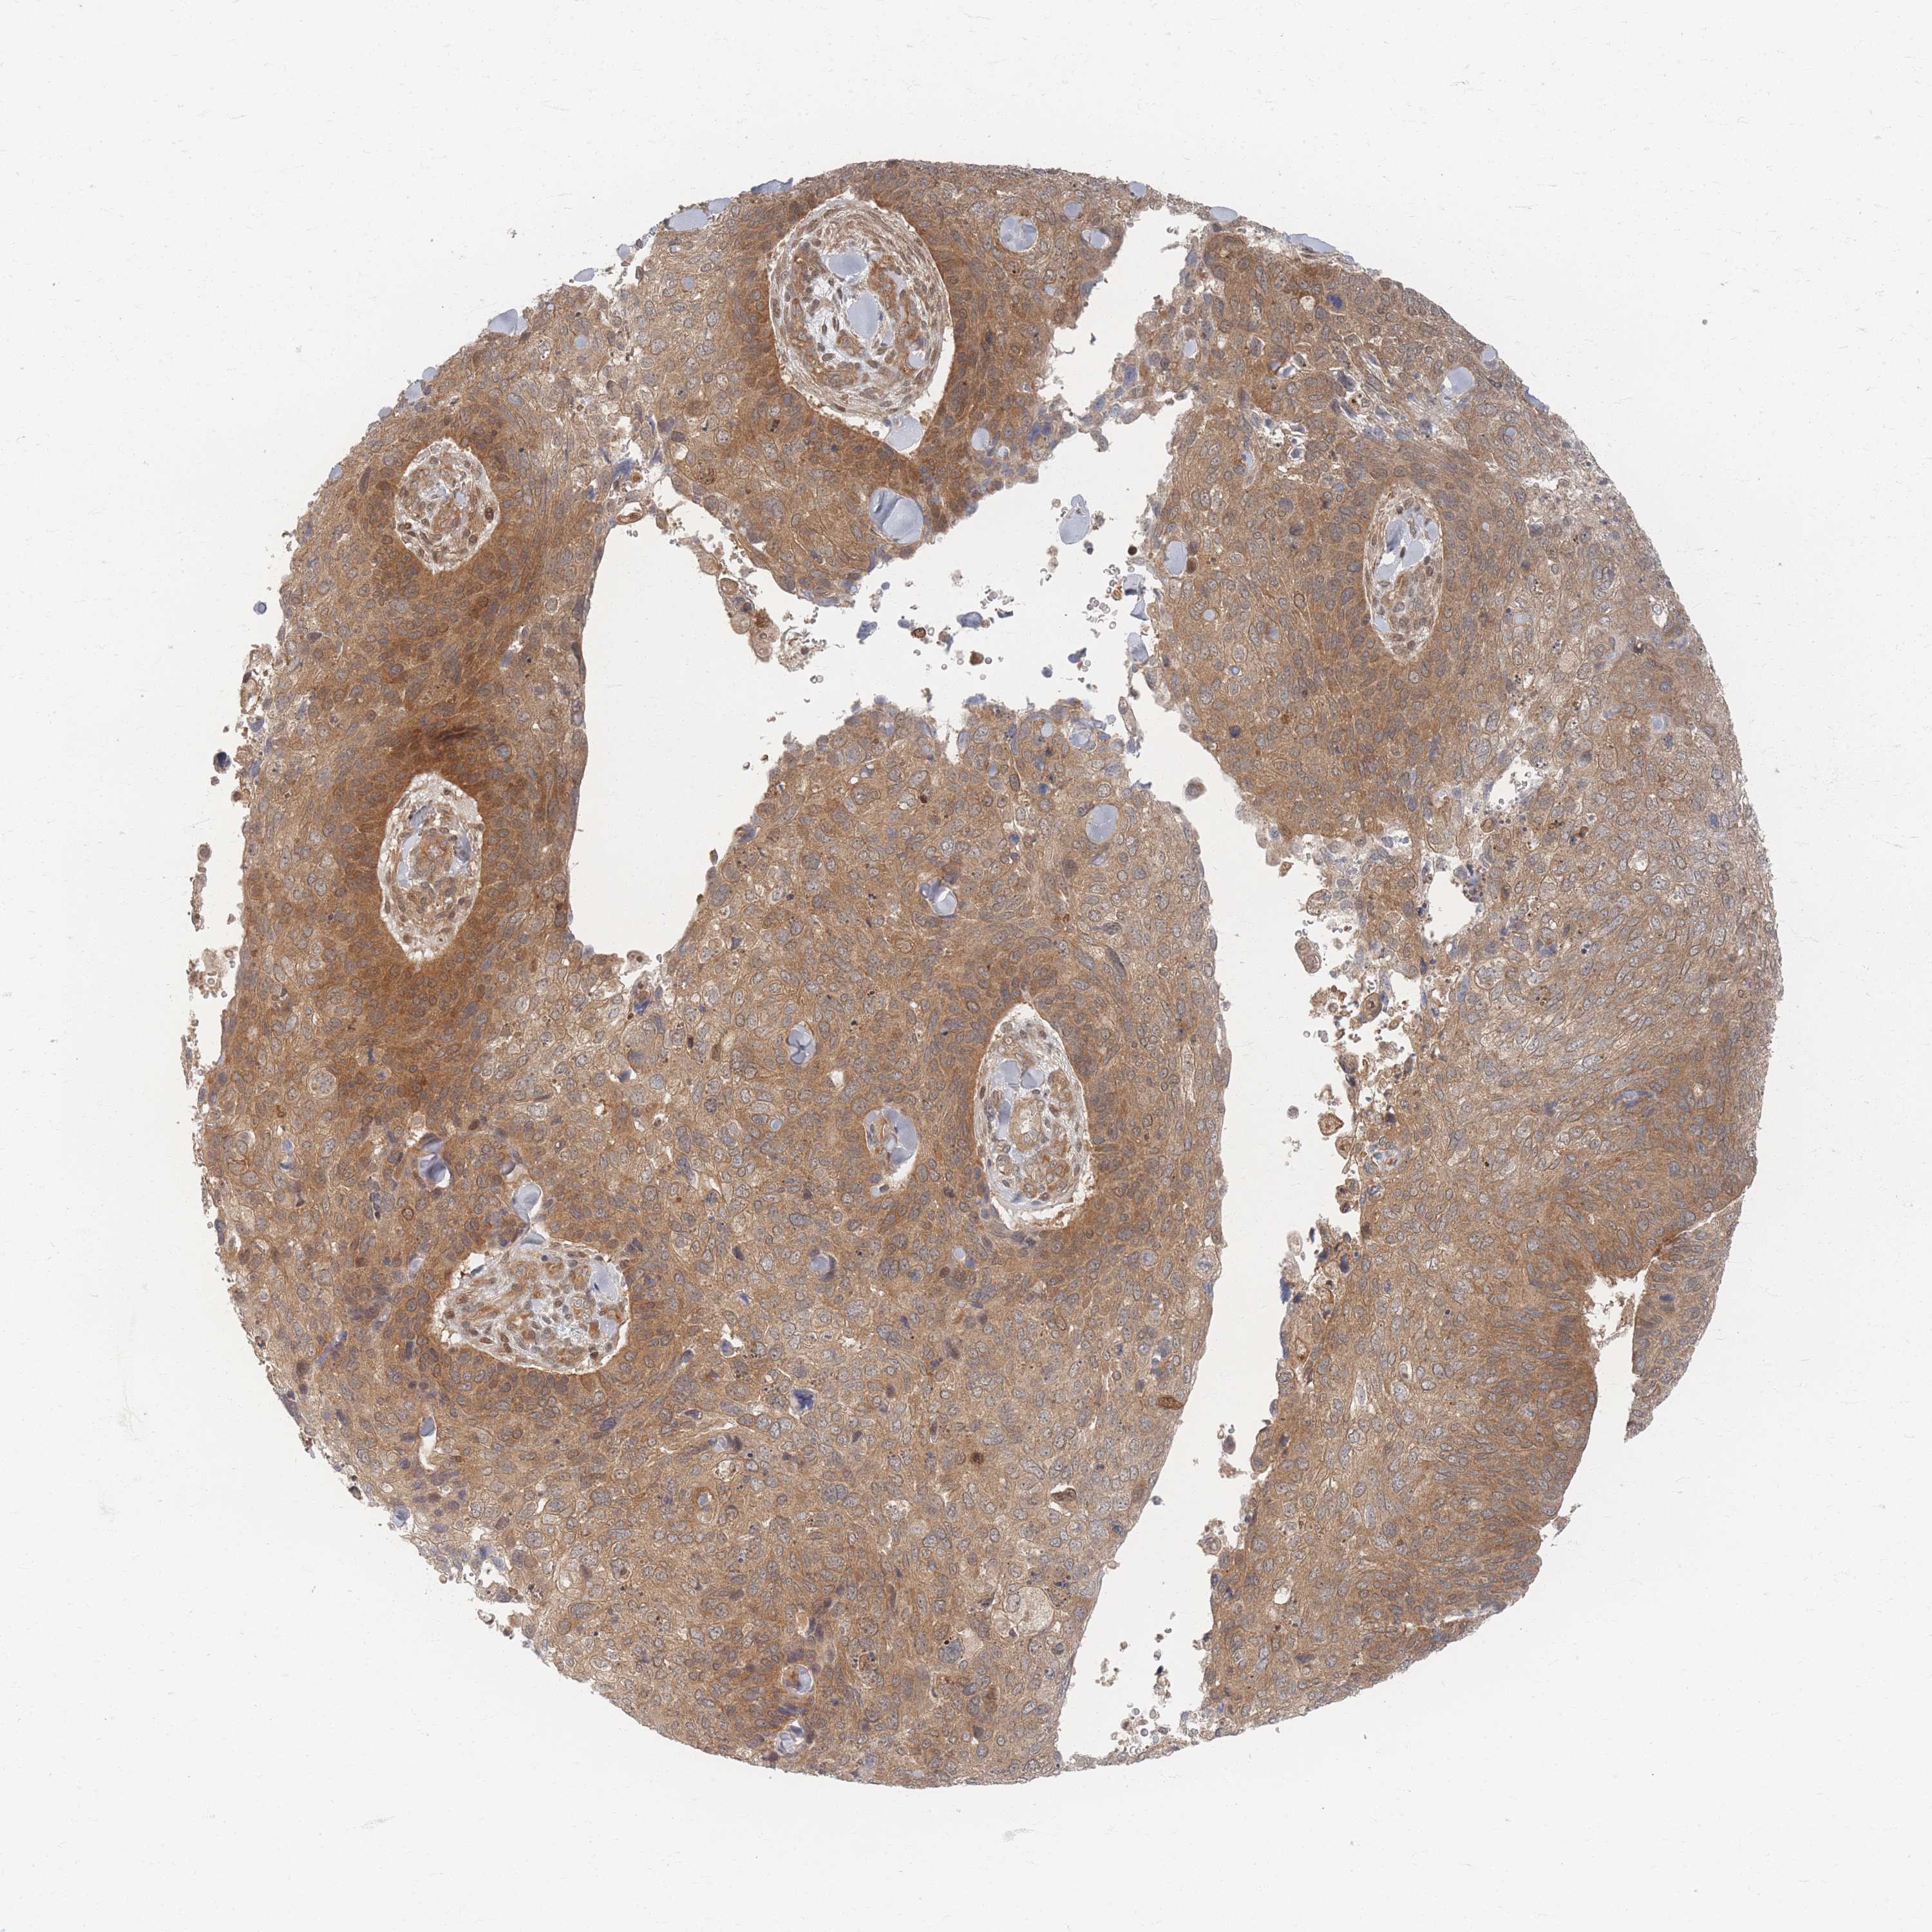

CANCER SKIN CANCER Show tissue menu

Basal cell and squamous cell cancer

SKIN CANCER - Protein expressioni

A mouse-over function shows sample information and annotation data. Click on an image to view it in a full screen mode. Samples can be filtered based on level of antibody staining by selecting one or several of the following categories: high, medium, low and not detected. The assay and annotation is described here.

Each image is clickable and will lead to virtual microscopy that enables deeper exploration of all samples and also displays staining intensity scores, fraction scores and subcellular localization as well as patient and tissue information for each sample.

Antibody HPA044220

Squamous cell carcinoma, NOS